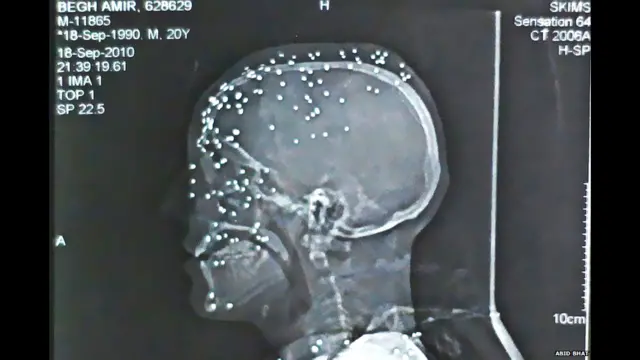

22 वर्ष के आमिर कबीर बेग के सिर का एक्सरे उनके सिर में पैलेट गन से लगी चोटों को दिखाता है.

बेग को ये चोटें सितंबर 2010 में उत्तरी कश्मीर के शहर बारामूला में हुए प्रदर्शनों के दौरान लगीं. उनका कहना है कि घर लौटते वक्त उन पर पैलेट गन से वार किया गया. इससे उनकी दोनों आंखों की रोशनी चली गई.